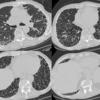

Honeycomb CT 4in1

Date: 01/06/2012

Views: 3187